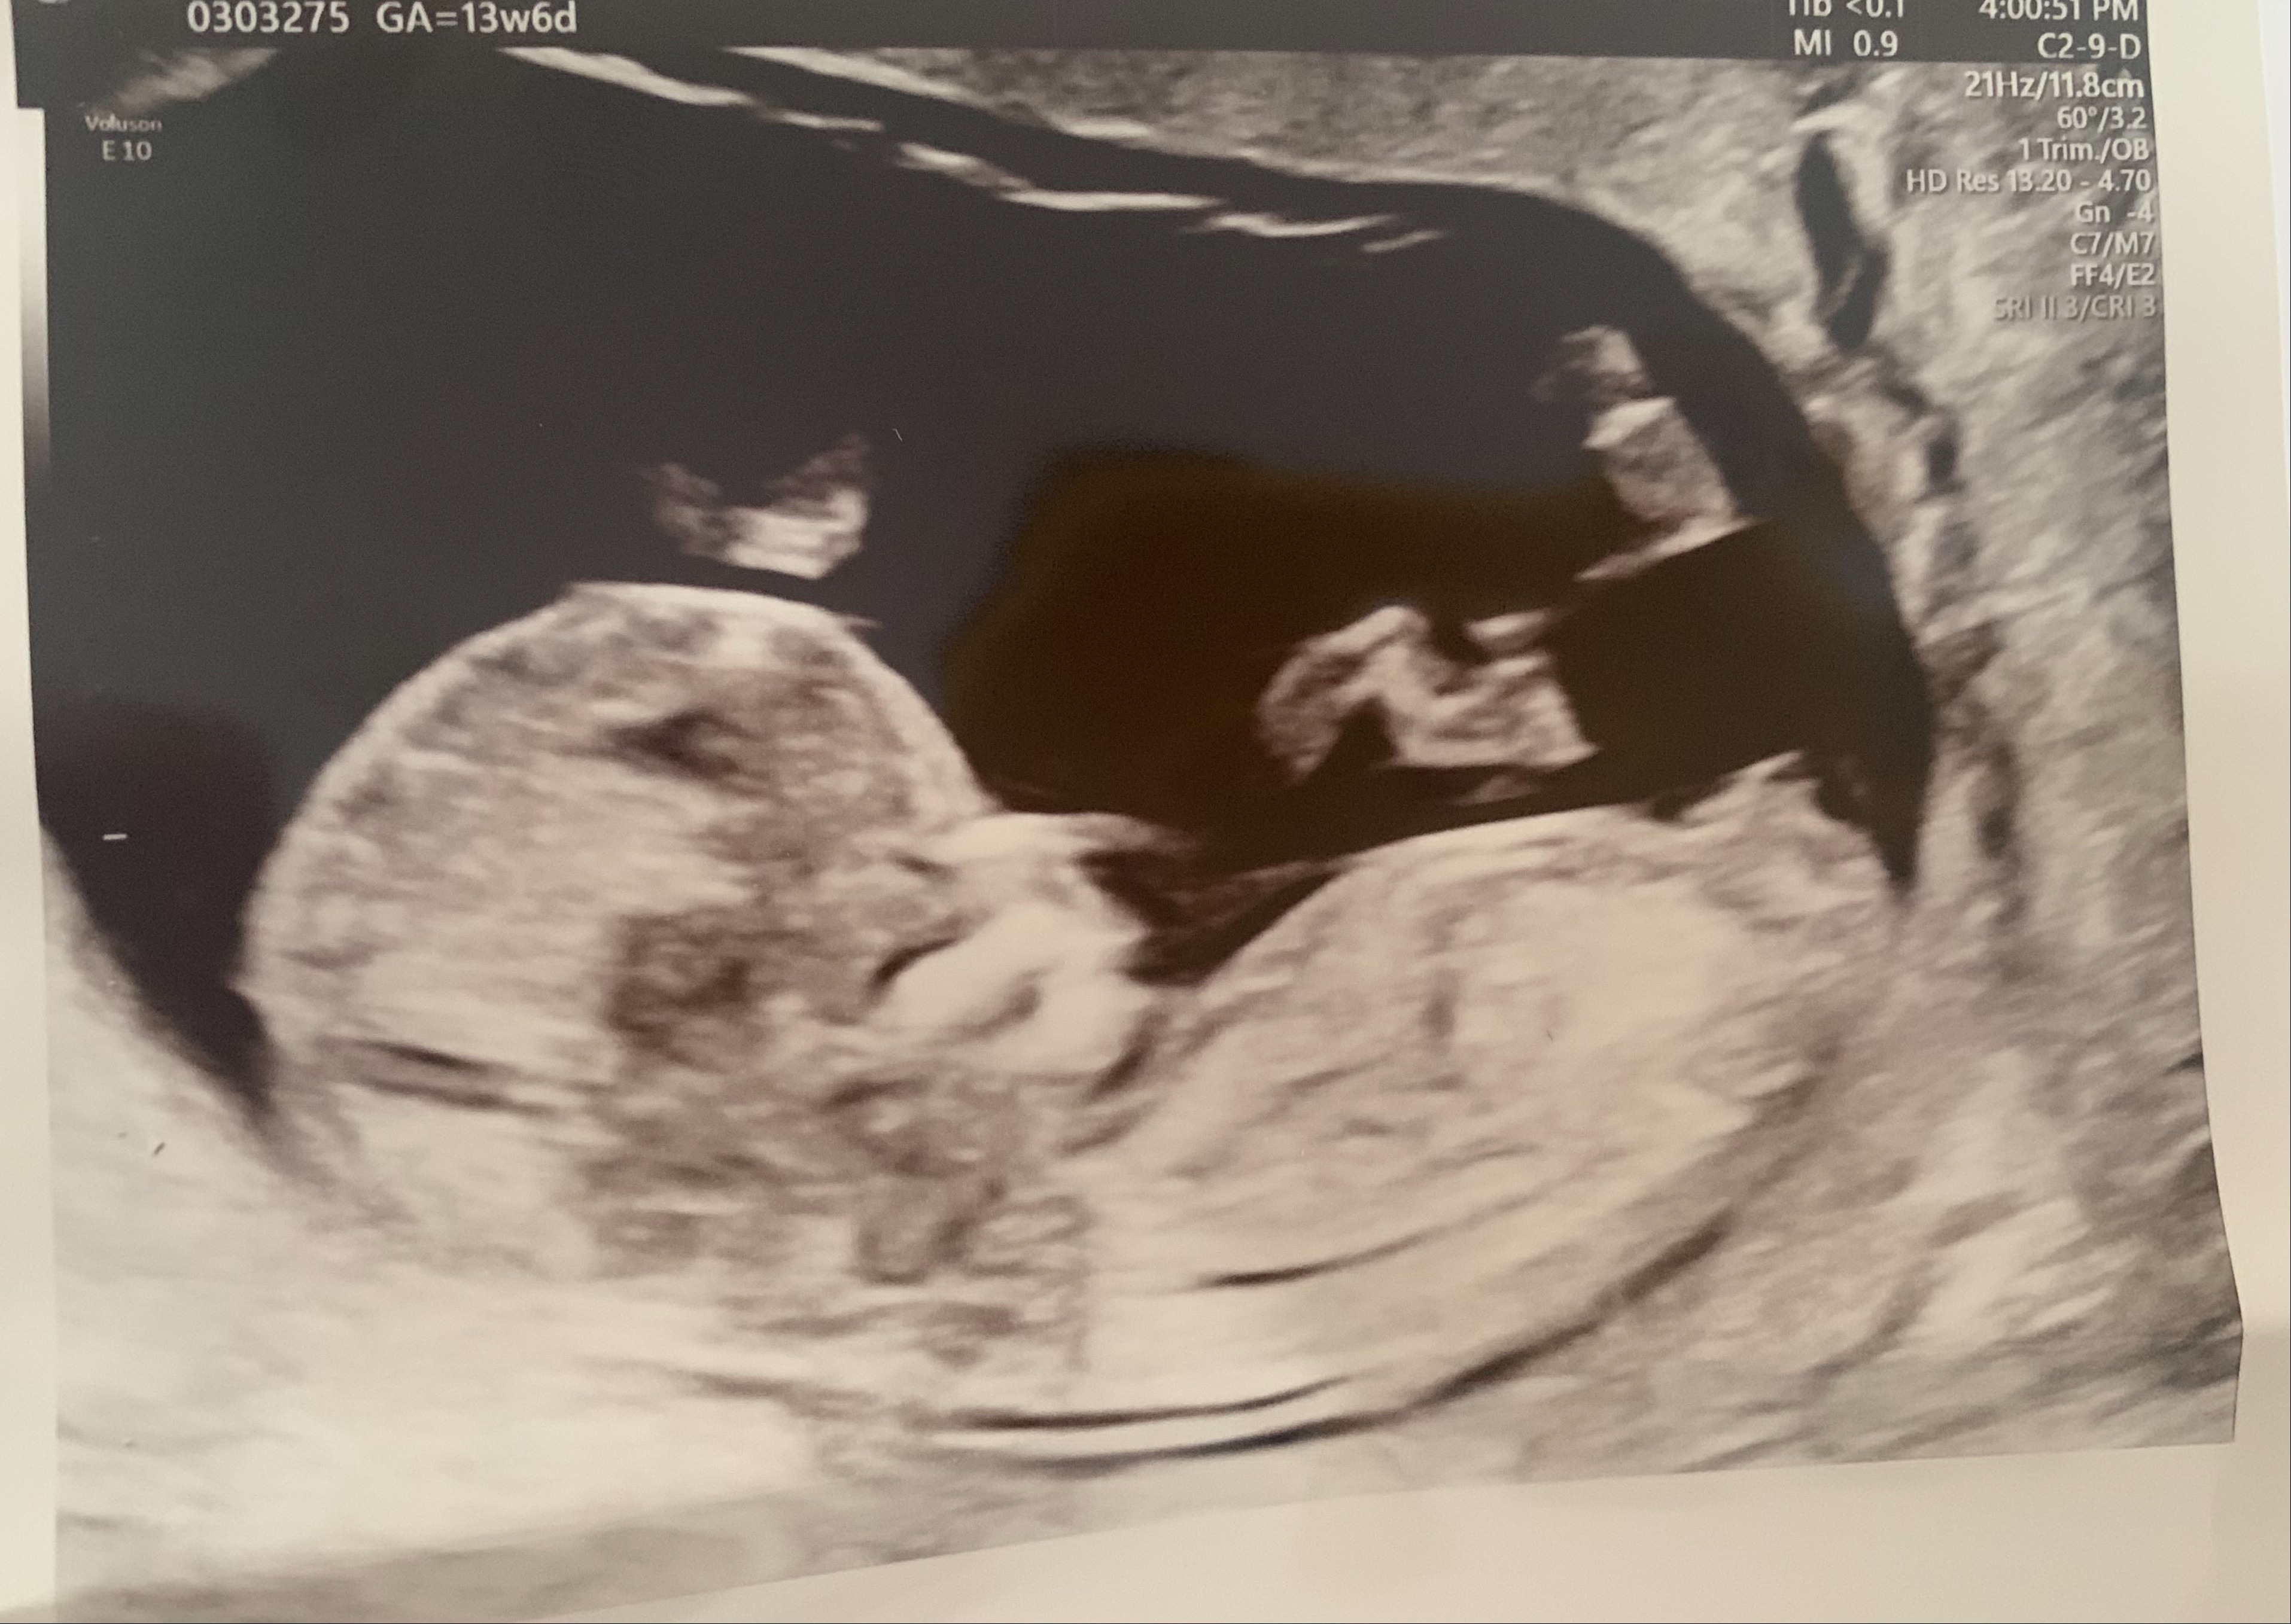

can i have a look at your ultrasound please at first

Dr Aqsa please see the ultrasound pics below

Please check now

Dr Nazish Ali please see the ultrasound reports

Doctors, please see the ultrasound pics below